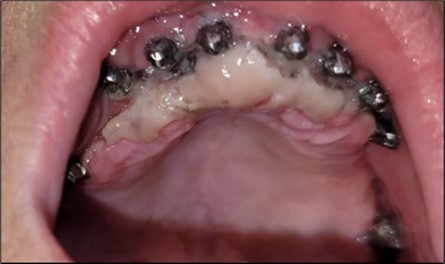

Clinically, we observe the exposure of the implants in the oral cavity with bacteria plaque on their surface, primarily due to the retentive surface of the implants. The exposure of the endosseous part of the two stage implants represents the starting point for mucositis and subsequently peri-implantitis (Figure 2). An important role is played by the occlusion of the prosthetic restorations and the way in which masticatory forces are transmitted to the implants. Prosthetic restorations with prominent vestibular cusps in contact with the opposing teeth, which during lateral movements lead to an increase in extrusive forces on the implant side (in this case, implants) (Figure 2a, b, c). A lingualized occlusion is preferred, where the masticatory forces are placed closer to the insertion axis of the implant.

Figure 2.Intraoral images of the exposed implants affected by peri-implantitis: (a) quadrant 3, vestibular view; (b) quadrant 2, vestibular view; (c) quadrant 4, vestibular view; (d) quadrant 4 after removal the prosthetic restoration and uncovering the implants, vestibulo-lingual view.